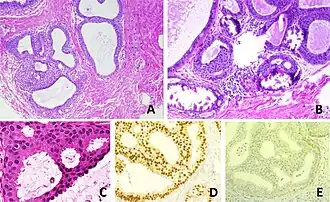

- A - One focus (< 2 mm) of two architecturally disarranged cross sections of tubuli showing a monotonous intraductal proliferation with secondary intraluminal architecture. Hematoxylin and Eosin stain.

- B - One area of an ADH with associated calcifications intraluminal. Hematoxylin and Eosin stain.

- C - Higher magnification of ADH shows low-grade nuclear atypia and monotonous cell proliferation along with secondary intraluminal architecture. Hematoxylin and Eosin stain.

- D - Strong and uniform expression of estrogen receptors (ER). ER immunohistochemistry.

- E - Lack of basal cytokeratins (CK5/6). CK5/6 immunohistochemistry.